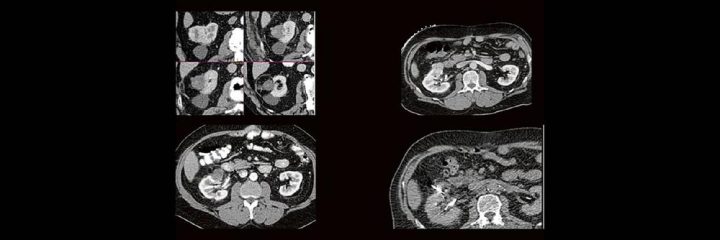

Dr. med. André ReisbergDr. med Sebastian Plößl Die bildgebende HNO-Diagnostik macht es Anfängern nicht leicht. Die Anatomie ist komplex und weniger intuitiv als in anderen Körperregionen. Normvarianten erschweren insbesondere in den Nasennebenhöhlen den Lernprozess. Sobald pathophysiologische Zusammenhänge verstanden und wichtige klinische Aspekte verinnerlicht wurden, gelingt es einen praxistauglichen, belastbaren Befund zu erstellen. Wo muss ich eigentlich hinschauen? Was will der Kliniker von mir wissen und warum? Begleiten Sie uns auf einer kooperativen Reise durch die NNH mit „Ach so!“-Garantie: GemeinsamWeiterlesen